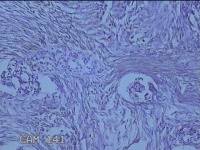

大腿肿物

性别

男

年龄

54岁

临床诊断

纤维瘤病

一般病史

无

标本名称

大体所见

灰白暗红色肿物1x0.8x0.2cm一个,表面糜烂。